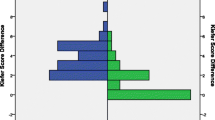

Initial pressure setting for the gravitational valve was adjusted by downregulation or upregulation to counteract signs of under- or over-drainage for a confined percentage of patients percutaneous with the corresponding programming tool. No pressure level adjustments as a matter of routine were performed. In total 166 GAV adjustments were carried out during the entire observation period (Fig. 3A–C) and the number of adjustments for individual patients ranged from 0 to 14 (mean 2.1 ± 2.8). Stepwise (2–10 cmH2O) GAV adjustment with consequentially altered pressure setting for upright body position after initial shunt insertion (Fig. 2C) had been carried out in 24 patients (31%) after 12 months, in 33 patients (42%) after 24 months, and in 50 patients (64%) at the time of last clinical follow-up (mean 63 months). Comparing the initially selected pressure level and the pressure level at the time of last clinical follow-up, the GAV unit was upregulated in 23 patients (31%), downregulated in 18 (24%), re-adjusted to initial pressure status after varying temporary alteration in 4 (6%), or remained completely unchanged in 29 (39%) of the patient collective. For 12 patients (16%) with signs of under-drainage GAV downregulation was ineffective and revealed underlying VPS malfunction during subsequently performed shunt revision surgery. Mean pressure setting for upright body position (sum of DPV and GAV) changed from initially 24.2 to 24.1 after 12 months, 24.6 after 24 months, and to 26.4 cm H2O at the time of last clinical follow-up (Fig. 2E). Quantity of pressure level adjustments for patients with IVH-related hydrocephalus (mean 2.3 adjustments) was increased compared to patients with hydrocephalus of any other etiology (mean 1.2 adjustments).

Percentage and number of performed A shunt revisions, B valve revisions, and C GAV-unit pressure level adaptions 12 and 24 months after initial VPS insertion as well as during the entire follow-up period (mean 63 months). D Reasons leading to initial shunt- or valve-revision surgery. E Alteration of mean pressure setting over time for the sum of DPV and GAV unit corresponding to upright body position

All 78 patient’s initial individual pressure level setting for upright body position (sum of differential pressure + gravitational pressure) illustrated by the light blue skyline and patients with at least one pressure level adjustment after 12 months (A), 24 months (B), and at the time of last clinical follow up (dark blue columns) (C)